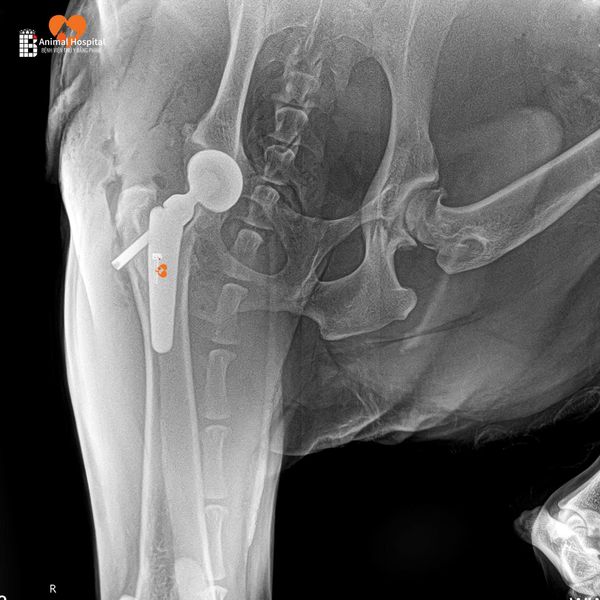

Ảnh X-quang hậu phẫu cho thấy:

- Implant được đặt đúng vị trí

- Trục khớp chuẩn xác

- Tiếp xúc xương tốt – là tiền đề lý tưởng cho sự phục hồi.